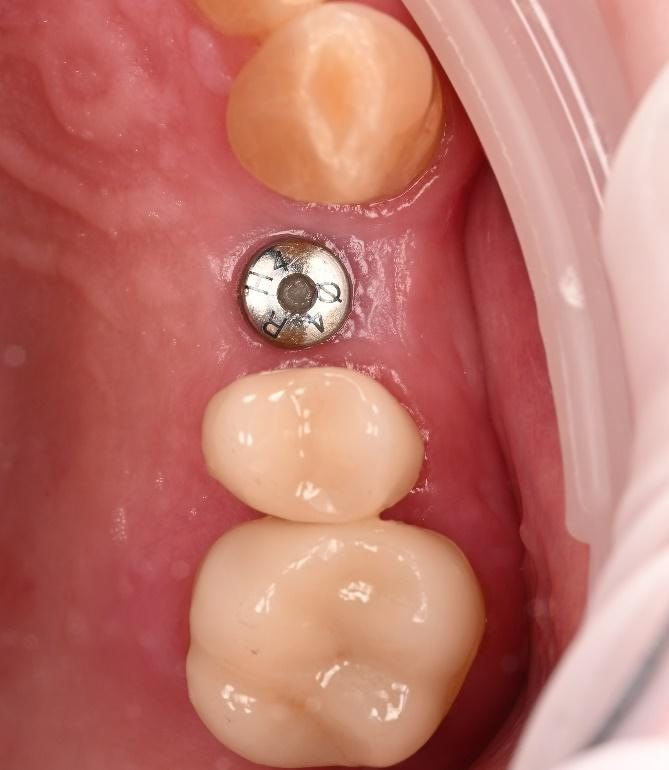

Three months after the implant surgery, a thorough post-operative assessment revealed excellent healing and implant stability.

Digital impressions were captured using the TRIOS 4 intraoral scanner, and the implant-supported crown was designed using 3Shape Design Studio.

Implant detection matches the scan body in the intraoral scan with the digital library. A colour scale is given to show the accuracy of the matching (Green is good).